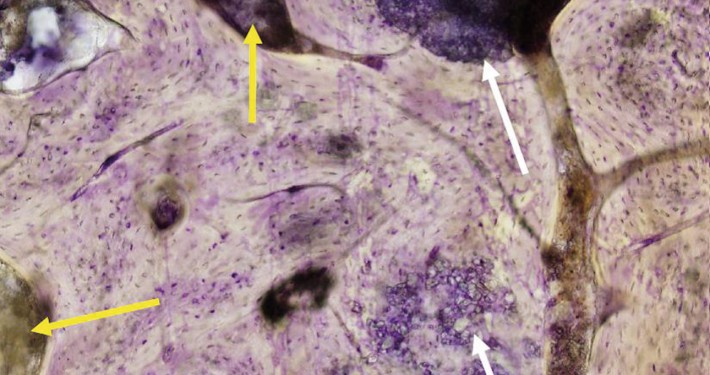

CERASORB® Foam is a highly porous composite made of porcine collagen (collagen complex) and pure-phase β–TCP granules of different sizes and densities. The collagen matrix embeds the granules and stabilizes them by virtue of its fibrous structure. This special combination of the two materials provides a granular phase of 85% by weight, and thus a high volume stability after degradation of the more rapidly resorbed collagen.

CERASORB® Foam is a highly porous material combination comprised of porcine collagen and pur–phase β–tricalcium phosphate granules (CERASORB®). This combination has a two-fold action. Collagen supports early phase of bone regeneration, while the high proportion of CERASORB® granulate ensures longer-term volume stability. The material is completely degraded over the long term, replaced by autologous bone, and thus creates the necessary stability for later implant restoration.